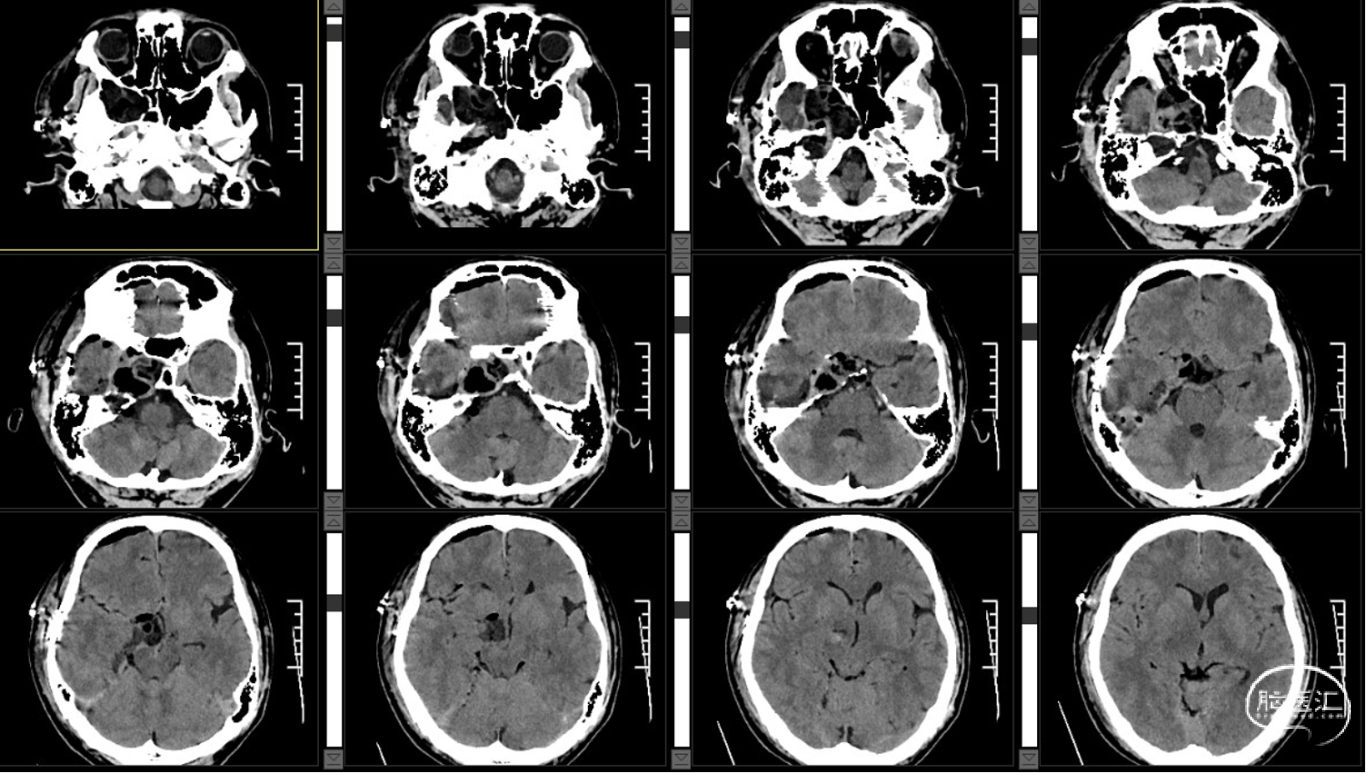

外院CT示:右侧颅底占位性病变,临近骨质部分吸收。